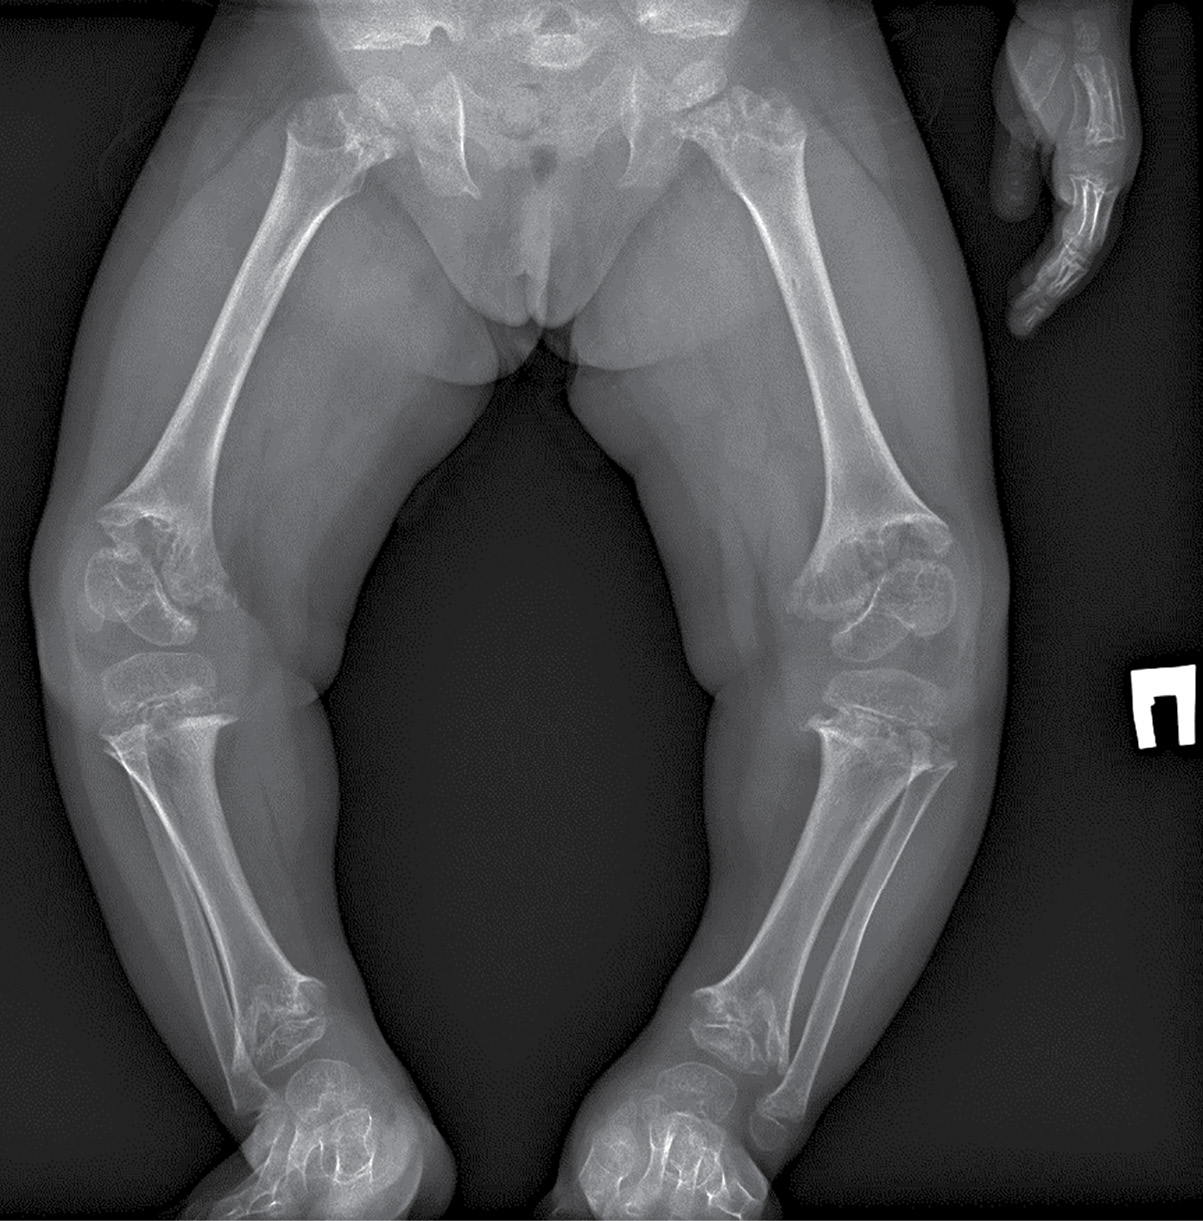

В биохимическом анализе крови клинически значимых изменений нет: кальций общий — 2,49 ммоль/л, кальций ионизированный — 1,28 ммоль/л, фосфор неорганический — 1,89 ммоль/л. В гормональном профиле уровень ИФР-1 соответствует возрастной норме — 81,7 нг/л (18,2–172,0). По данным рентгенографии нижних конечностей, в прямой проекции выявлена выраженная варусная деформация коленных суставов. Метаэпифизы всех костей, образующих правый и левый коленные суставы, расширены, вздуты. Соотношения в суставах неправильные (больше — в правом суставе). Суставные поверхности неровные, нечеткие, суставные щели неравномерные, расширены (рис. 1–2).

Рисунок 2. Рентгенография правого коленного сустава в боковой проекции.